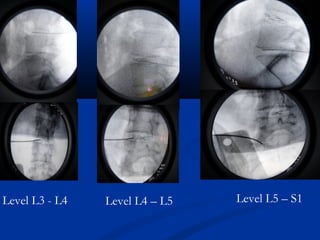

One level

Discoplasty

Level L3 - L4 Level L4 – L5 Level L5 – S1

Level L3 -L4 Level L4 – L5 Level L5 – S1